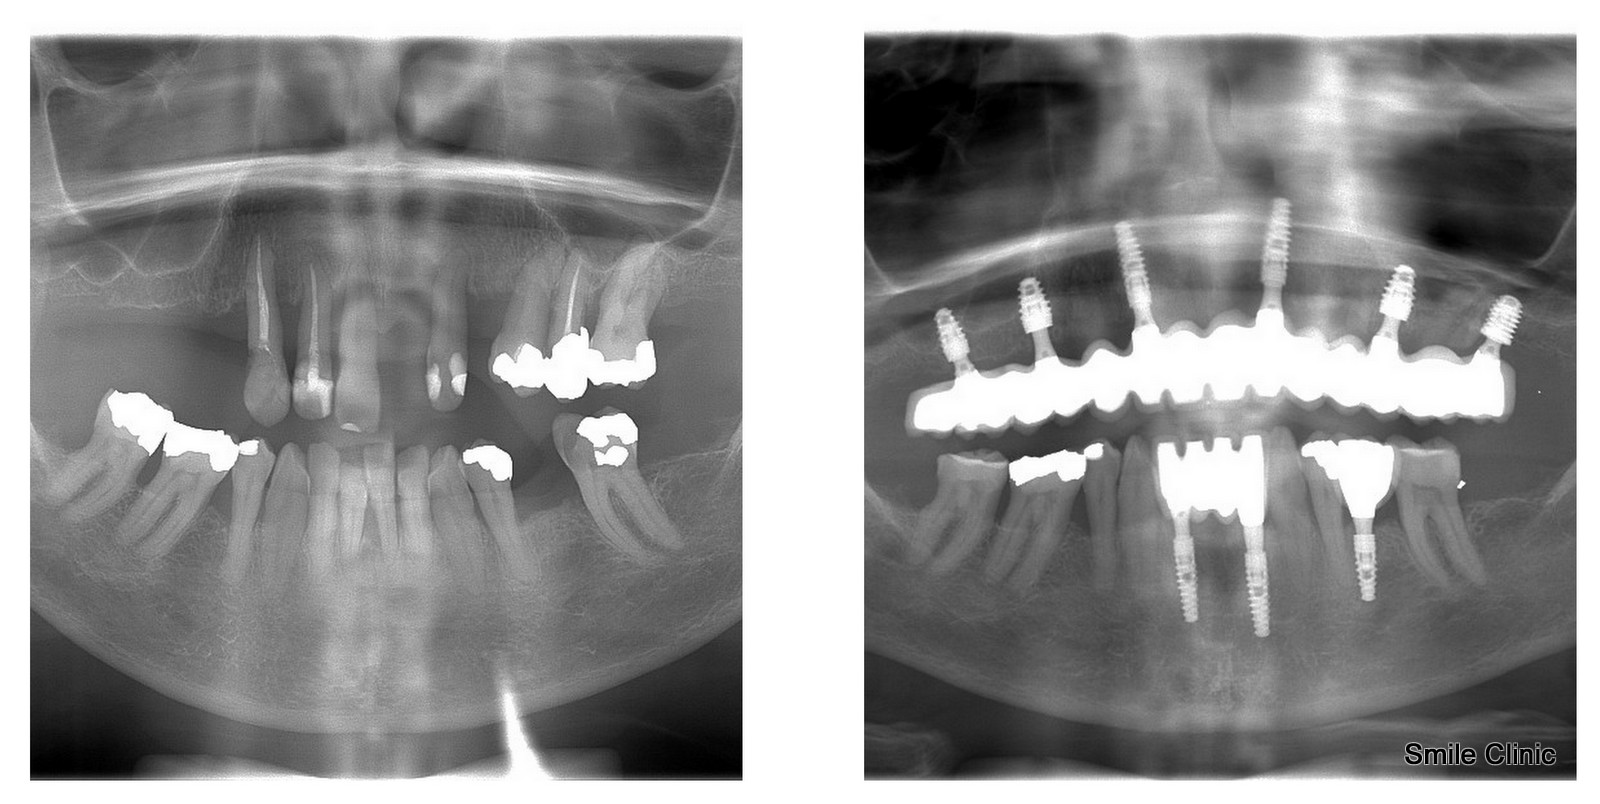

If you have a look at the X-ray here, you’ll see the “before” state of teeth and then after:

6 dental implants, abutments, some tooth extractions and 14 crowns for the upper jaw, and 3 dental implants for the bottom jaw and 6 crowns.

Putting new implants in her upper jaw gave her a complete face lift as well on both sides once the weakened jawbone was healed with full healthy bone.